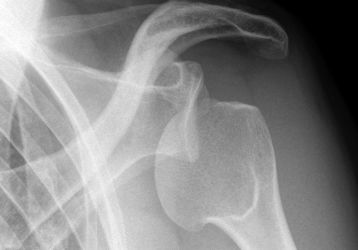

Воспаление сухожилий плечевого сустава или тендинит надостной мышцы: лечение, симптомы, формы и стадии заболевания

Что такое тендинит плечевого сустава: лечение, причины болезни, симптомы, формы и стадии тендинита плеча. Диагностика заболевания, как лечить воспаление сухожилий плеча.